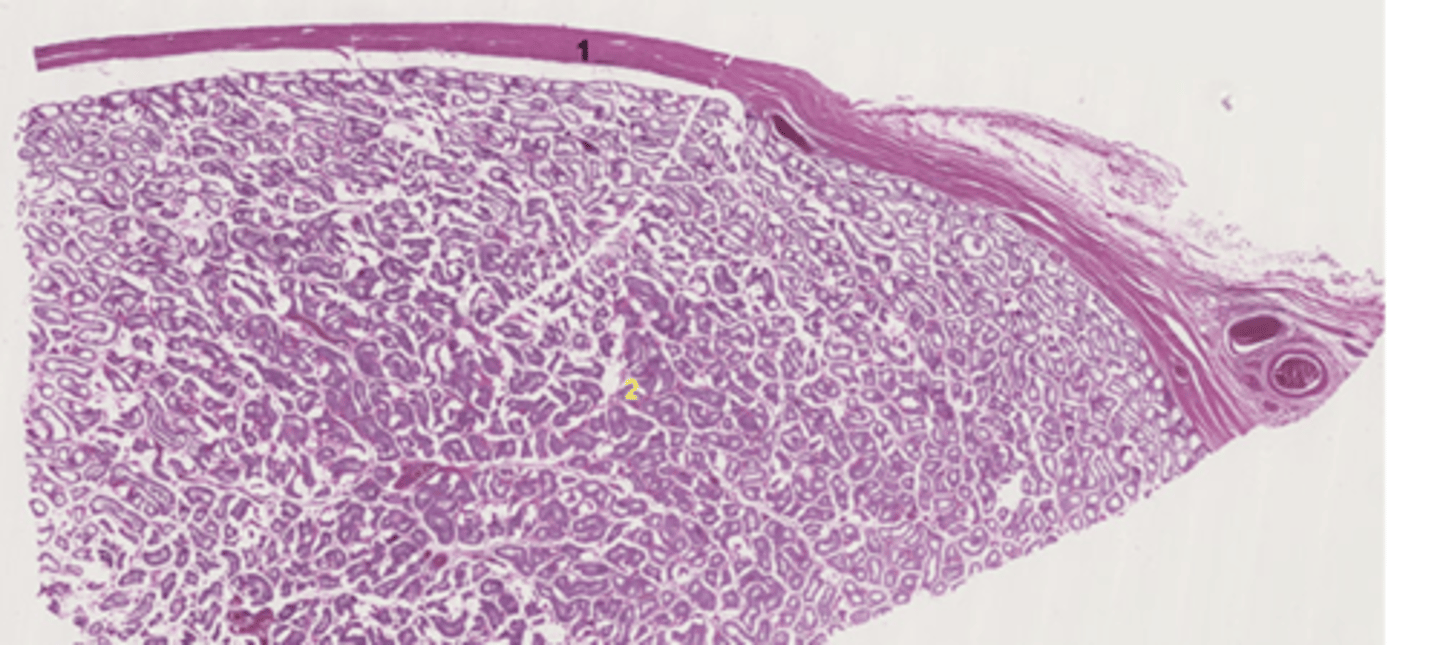

cortex

A

medulla

B

surface epithelium

tunica albuginea

2

seminiferous tubule

basement membrane

thin membrane surrounding the tubule

leydig cell

lobule

tunic albuginea